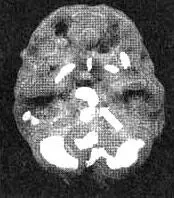

Когда Ли Анн вновь приехала ко мне, она все еще отказывалась поверить, что с ней «что-то не так», и по-прежнему отказывалась возобновить прием препарата. После того как я назначил ей исследование мозга, чтобы оценить состояние ее глубокой лимбической системы, я показал ей область повышенной активности в этой части мозга. Это стало для нее убедительным доказательством в пользу приема лекарства.

Мозг Ли Анн — депрессия

Трехмерное изображение снизу активный мозг Обратите внимание на повышенную - фото 32

Трехмерное изображение снизу — активный мозг. Обратите внимание на повышенную активность в лимбической системе.